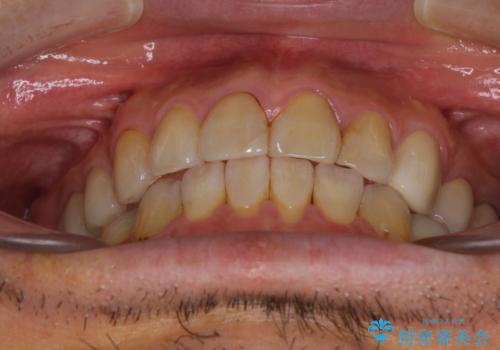

痛みは速やかに引き、銀歯や黒く変色したむし歯がセラミッククラウンで自然な色合いに仕上がり、患者様には大変満足していただきました。